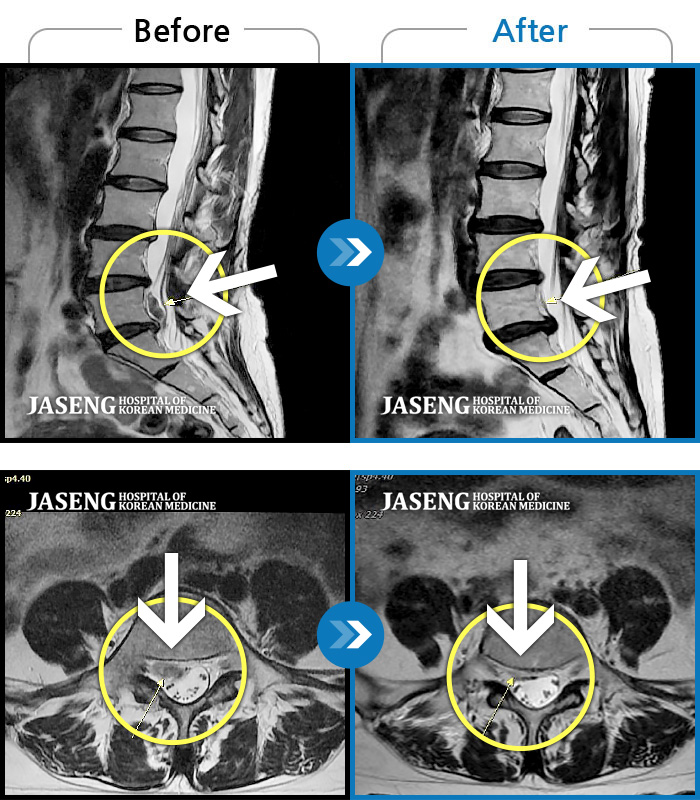

허리디스크

울산 · 정운석 원장

좌측 하지 외측이 저리면서 당김증상 및 감각둔화

촬영시기

2016.12.22 ~ 2022.11.24

2022.12.09